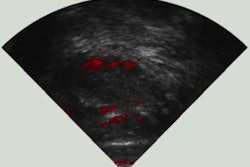

Photoacoustic imaging combines light and sound, sending near-infrared laser pulses into the brain and generating heat that converts to ultrasound waves, according to a statement released by the university. No contrast agent is necessary, according to principal investigator Yun Jing, PhD.

The prototype Jing and colleagues are developing wraps around the head and generates a sound signal that can penetrate the skull. The scanner could be used to identify injuries to the brain developmental disorders in both children and adults, and future versions of the device could be used with other parts of the body, such as the chest, to detect breast cancer, Jing said in the statement.